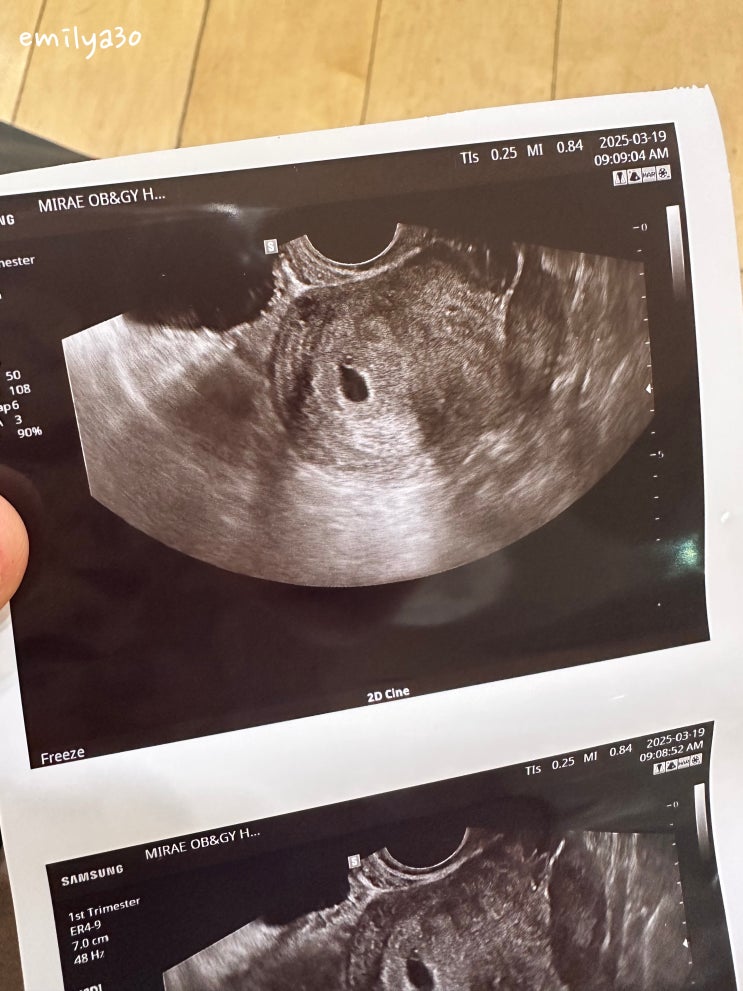

임신 6주차 / 심장소리 듣기 성공! / 담당 원장님 변경

임신 6주차, 심장소리 듣기 성공 ! / 담당 원장님 변경 250301 동결배아 5일배양 자연주기 이식 250312 2차...